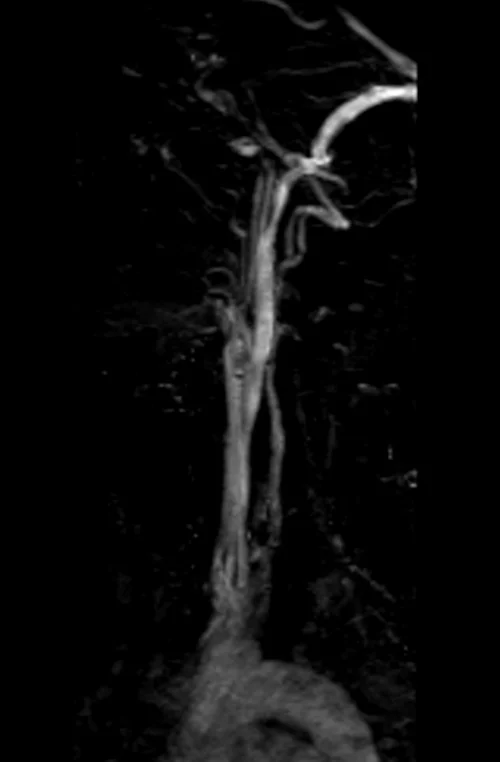

mra neck vascular localizer image - MRI